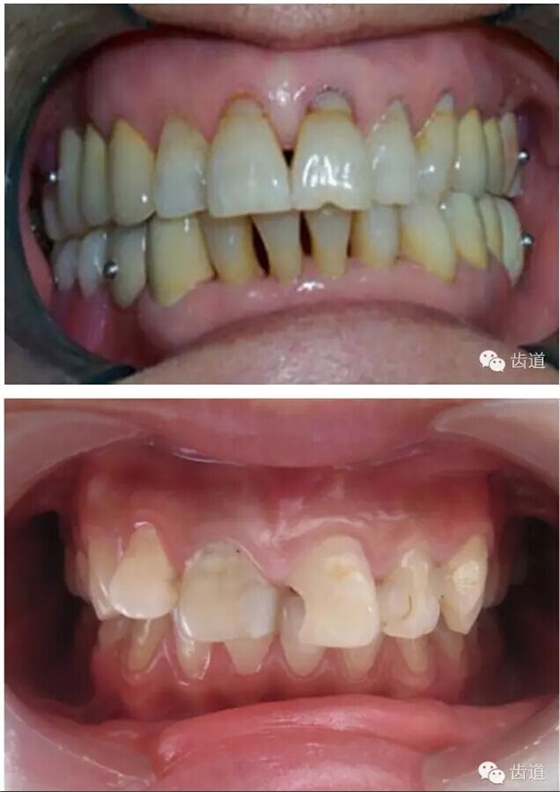

74.jpg

75.png

76.png

77.png

78.png

79.png

80.png

81.png

82.png

83.png

84.png

85.png

86.png

87.png

88.png

89.jpg

90.png

91.png

92.png

93..jpg

94.png

95.jpg

96.png

97.png

98.png

99.jpg

100.png

101.png

102.png

103.jpg

104.png

105.png

106.png